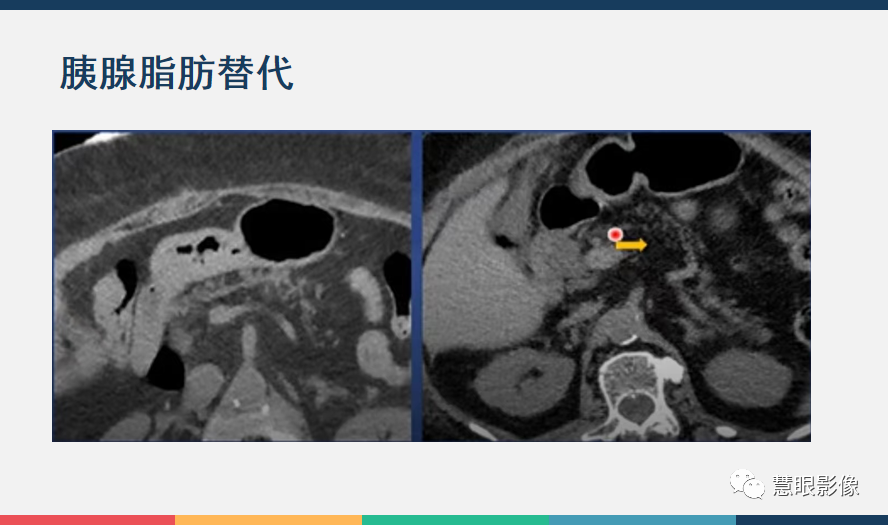

【PPT】胰腺解剖变异、发育异常及相关病变影像评估-3